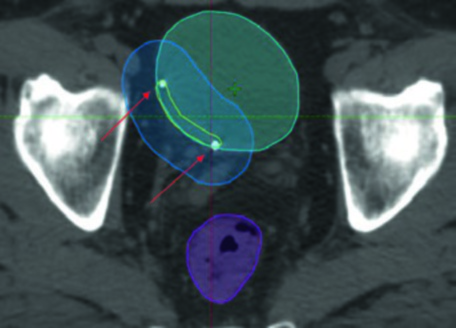

En la práctica, la planificación del boost vesical requiere marcadores fiduciales de oro implantados en la periferia del lecho de resección. Estos fiduciales permiten el registro diario con precisión submilimétrica. Observe cómo el PTV boost (azul) envuelve el lecho de TURBT (amarillo) con margen de 1 cm, mientras el recto (magenta) y el intestino (verde) se protegen mediante la conformación IMRT. Las flechas señalan los fiduciales que sirven como objetivos principales para la guía por imagen diaria.

El protocolo de guía por imagen varía según la institución, pero sigue una lógica consistente. Durante la fase inicial se realiza imagen kV diaria con match óseo y al menos CBCTs semanales para verificar la posición vesical. En la fase de boost, el estándar aumenta: imagen kV diaria con match a fiduciales y/o CBCT diario. Sin fiduciales, el CBCT diario se torna obligatorio en la fase de boost.